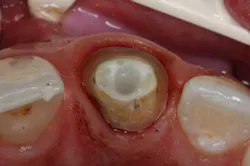

The documented accessory post technique helps address the problem of restoring a wide, oval, flared, or otherwise large or irregularly shaped root treatment spaces. In combination with a master fiber post, and any resin cement and core composite, this technique offers a strong, low-modulus, esthetic, radiopaque, one-appointment, reversible alternative to cast posts. The concept of multiple posts is similar to the placement of gutta percha cones.